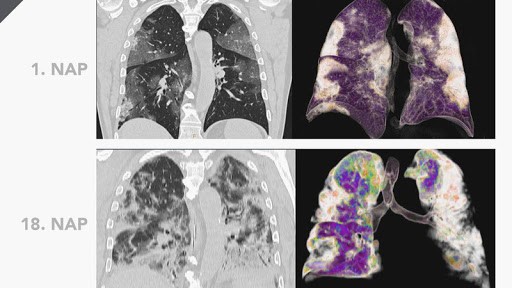

Covid-19 beteg tüdeje: CT és PET-felvétel

Forrás: Semmelweis Egyetem Orvosi Képalkotó Klinika

A bal oldali CT képeken a sötét tüdőrész mutatja a légtartó területeket, a világos eltérések pedig a vírusfertőzés által érintett tüdőgyulladásos területeket. A jobb oldali fuzionált (egymásra vetített PET és CT) felvételeken az utóbbi gyulladásos eltérések zöldes-sárgás színnel ábrázolódnak. Látható, hogy az egészséges, légtartó tüdő sötét, ahol a léghólyagok gennyel, vagy gyulladásos izzadmánnyal kitöltöttek, ott világos. A gyulladás elmúltával ezek teljesen gyógyulhatnak, de az is előfordulhat, hogy kis hegesedés marad a helyén.